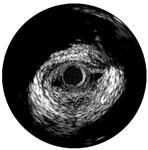

An example of OCT showing a stent with neointimal growth over the stent struts. The struts appear as bright spots.

While IVUS provided better information than angiography alone, poor image quality led manufacturers to begin researching other imaging technologies. OCT was brought to market first in Japan by LightLab Imaging in 2008, and launched in the United States in May 2010. OCT uses near infrared light to project images of the vessel wall and lumen. Due to the high frequency associated with the light signal, image resolution is 10 times greater than that of IVUS, leading to better views of stent apposition and thrombus detection. Reduction in stent mal-apposition, which is associated with late stent thrombosis (LST) and better resolution for neo-intimal tissue growth and in-stent restenosis are some of the key advantages of OCT.